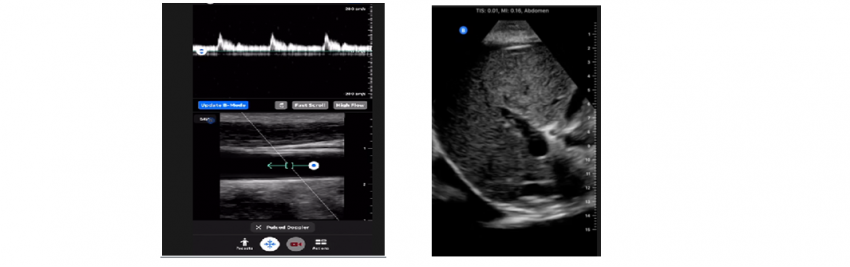

If we talk about the software, it is universal, without the hidden submenus - everything is directly on the display. One inconvenient option is that you have to connect the transducer to the gadget manually (via the additional menu at the top of the program), but this is also quite fast and can be done right on the way to the patient's bedside.

Here are some clinical images from which you can evaluate the quality of visualization and the interface of the program.

The functionality of Ramzed linear transducer software includes presets for thyroid and breast examinations, programs for carotid arteries and peripheral vascular examinations, as well as presets for small organs and superficially located structures.

As for the Ramzed convex probe, there are usually default presets for wide abdominal examinations, prostate examinations, gynecological and obstetrical programs.

The clinical calculation package is available only for superficial obstetrical examinations (not for specialized examinations). As for the other programs, the usual calculations to measure the distance, area and volume of the structures are laid there.